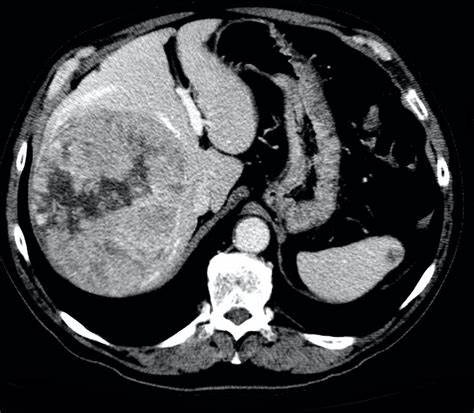

在中国,发病率较高的癌症包括肺癌、胃癌、肝癌、乳腺癌和食管癌等。